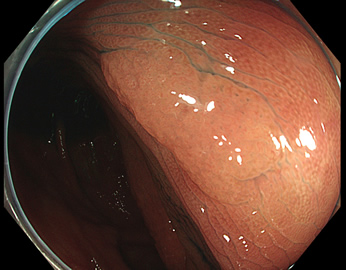

特に、下のような「Ub型(全く凸凹の無い完全に平坦な病変)」は、以前は「ほとんど見つからなかった」のが、TXIを使うようになってから「日常的に」見つかるようになりました。

通常観察 TXIモード

青い色素は追加していません![]()